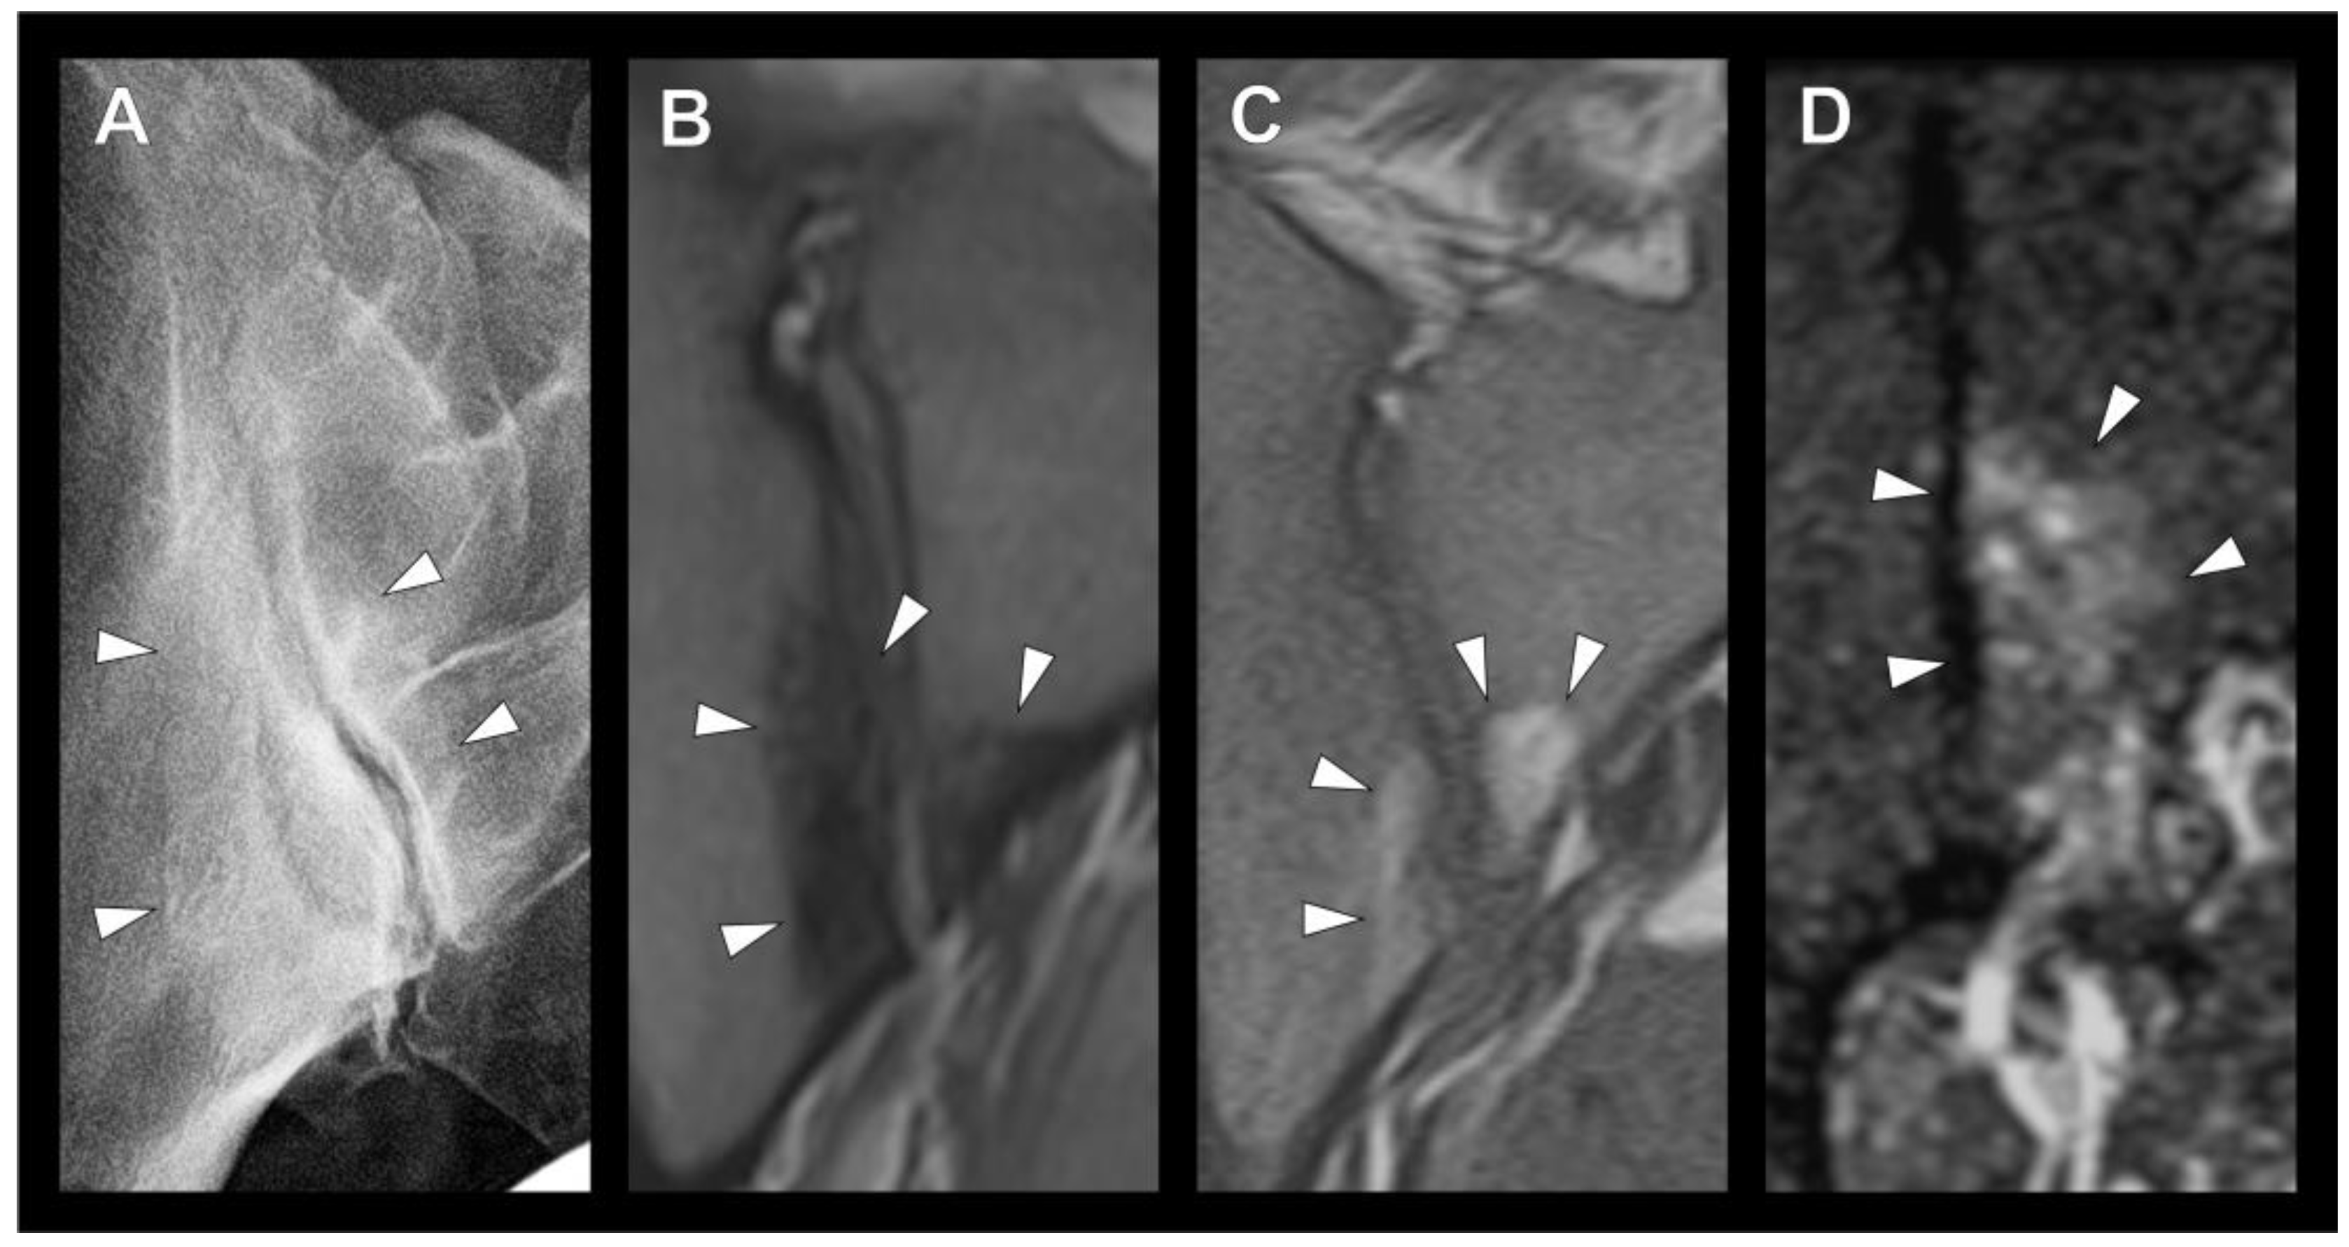

3.2. Sclerotic Lesions in Typical Location of Osteitis Condensans Ilii

3.3. Imaging Modality and Inter-Rater Reliability